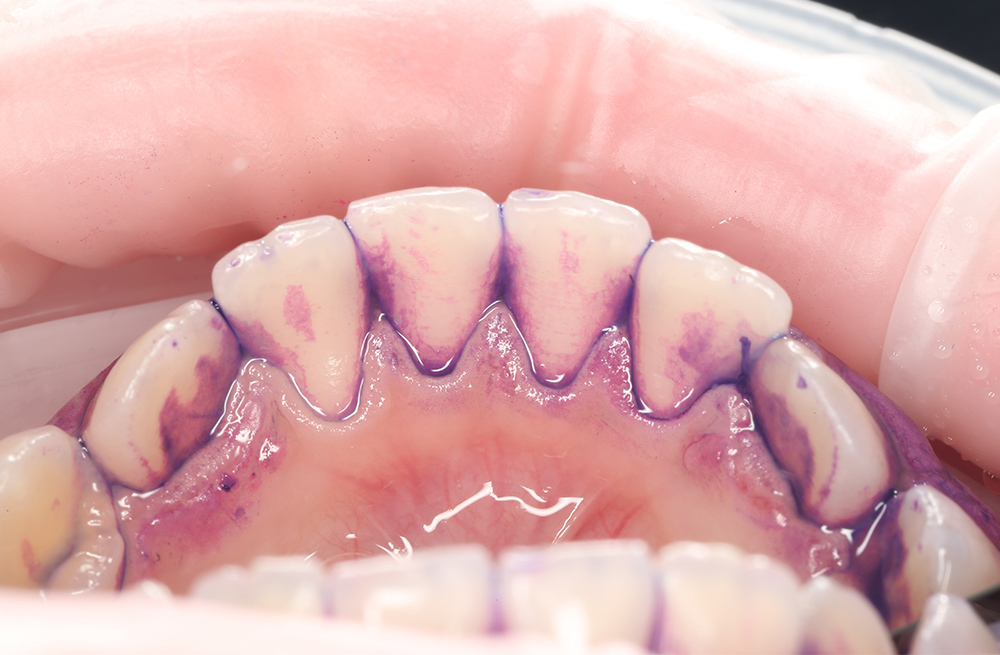

Удаление мягкого и пигментированного налёта у подростка с использованием Air-flow